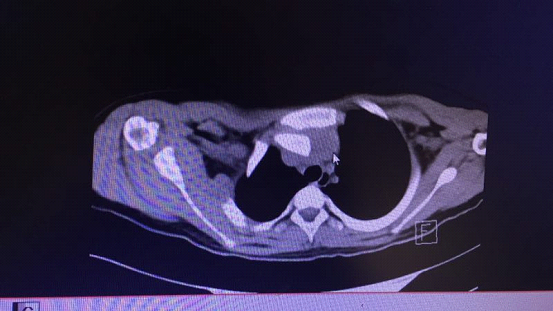

▲CT三维重建显示右胸锁关节后脱位

由于小云锁骨胸骨端向后严重移位,压迫了胸腺、气管、头臂动脉、头臂静脉,且移位的锁骨胸骨端离头臂静脉仅2mm,距头臂动脉5mm,加上双肺多发渗出挫伤,病情十分危急。要挽救小云的生命,需紧急进行急诊手术。